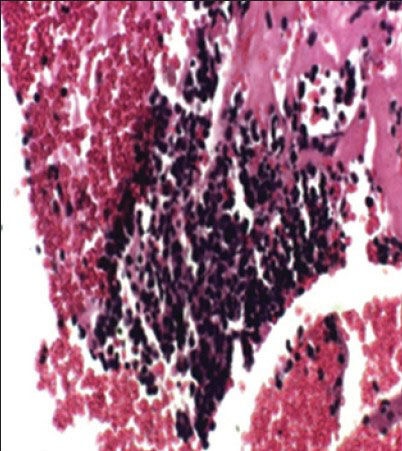

The case we present here is a 13-year-old boy who presented with the complaints of left lower limb weakness for 5 months and low back pain for 6 months. Hemogram and biochemical parameters were normal except lactate dehydrogenase (LDH) showing value of 96.40/IU/L, magnetic resonance imaging of the spine showed a large mass in presacral lesion (8 cm × 7 cm × 9 cm), with destruction of the sacrum (S2 S3 and S4) with interspinal extension. Bone scan showed multiple pelvic bone lesions, radiograph of chest, ultrasound of abdomen, pelvis and electrocardiogram were within normal limits. Bone marrow was not involved. Fine-needle aspiration cytology of the mass proved it to be a small round cell tumor. Immunohistochemistry for MIC2 was positive. Synaptophysin was inconclusive and leukocyte common antigen, desmin were negative [Figure [Figure1a1a and andbb].

| Figure 1b:Cell block of Ewing's sarcoma positive for MIC2